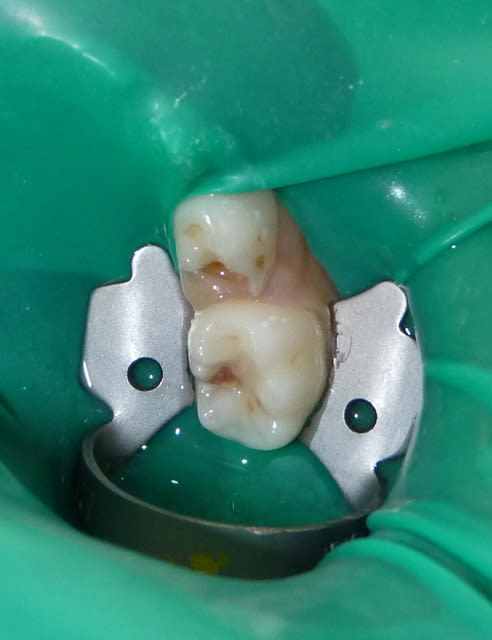

Je ne sais pas si c'est à cause de cela ou bien de l’anesthésie transpapillaire : ce matin, jolie nécrose d'une papille, indolore.

Sur la seconde photo, un crampon dentelé sur dent temporaire (même patient mais secteurs différents).